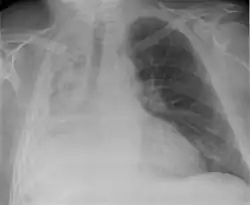

Atelectasis of a person's right lung | |

Atelectasis is the partial collapse or closure of a lung resulting in reduced or absence in gas exchange. It is usually unilateral, affecting part or all of one lung.[2] It is a condition where the alveoli are deflated down to little or no volume, as distinct from pulmonary consolidation, in which they are filled with liquid. It is often referred to informally as a collapsed lung, although more accurately it usually involves only a partial collapse, and that ambiguous term is also informally used for a fully collapsed lung caused by a pneumothorax.[1]

Clinically significant atelectasis is generally visible on chest X-ray; findings can include lung opacification and/or loss of lung volume. Post-surgical atelectasis will be bibasal in pattern. Chest CT or bronchoscopy may be necessary if the cause of atelectasis is not clinically apparent. Direct signs of atelectasis include displacement of interlobar fissures and mobile structures within the thorax, overinflation of the unaffected ipsilateral lobe or contralateral lung, and opacification of the collapsed lobe. In addition to clinically significant findings on chest X-rays, patients may present with indirect signs and symptoms such as elevation of the diaphragm, shifting of the trachea, heart and mediastinum; displacement of the hilus and shifting granulomas.[13]